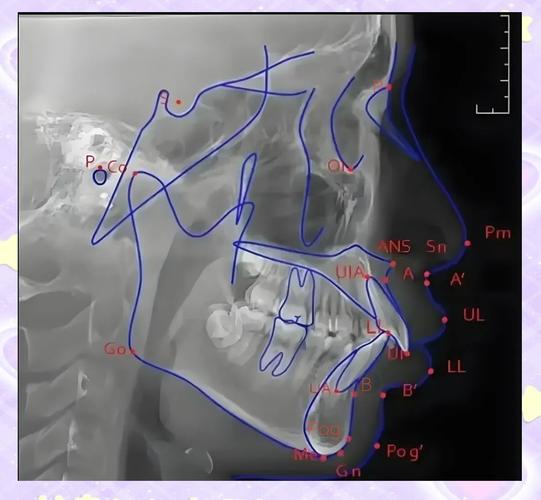

z角的测量需基于标准化的头颅侧位片,拍摄时要求患者处于自然头位(与地面平行)、唇部自然放松、无夸张表情或紧闭动作,以避免软组织变形影响结果,具体测量步骤包括:首先在X线片上标记关键解剖点——眶耳平面(FH平面)由眶下缘点(Or)与耳点(Po)连线确定,代表颅部的基准平面;软组织颏前点(Pos)为软组织颏部最前凸点;上唇突点(Ls)为上唇皮肤黏膜交界处最前点,随后连接Pos与Ls,该线与FH平面向后延伸线形成的夹角即为z角,使用专业头影测量软件(如Dolphin、V cep)或电子量角器可精确测量角度值,通常以度(°)为单位,为明确测量要点,现将关键解剖点及定义总结如下:

z角的正常值范围存在一定个体差异,研究表明成人z角正常值约为70°-85°,儿童因生长发育尚未完成,正常值略低,约为65°-80°,z角过大(如>85°)通常提示上唇相对后缩,可能伴随面型凹陷;z角过小(如<65°)则提示上唇前突,常见于骨性Ⅱ类错或上颌前突畸形,值得注意的是,z角需结合骨骼指标(如ANB角、SNA角)及软组织其他参数(如鼻唇角、颏唇沟深度)综合分析,例如骨性Ⅲ类错患者可能因下颌前突导致z角减小,但实际上唇突度可能正常,此时需区分骨骼与软组织因素对侧貌的影响。